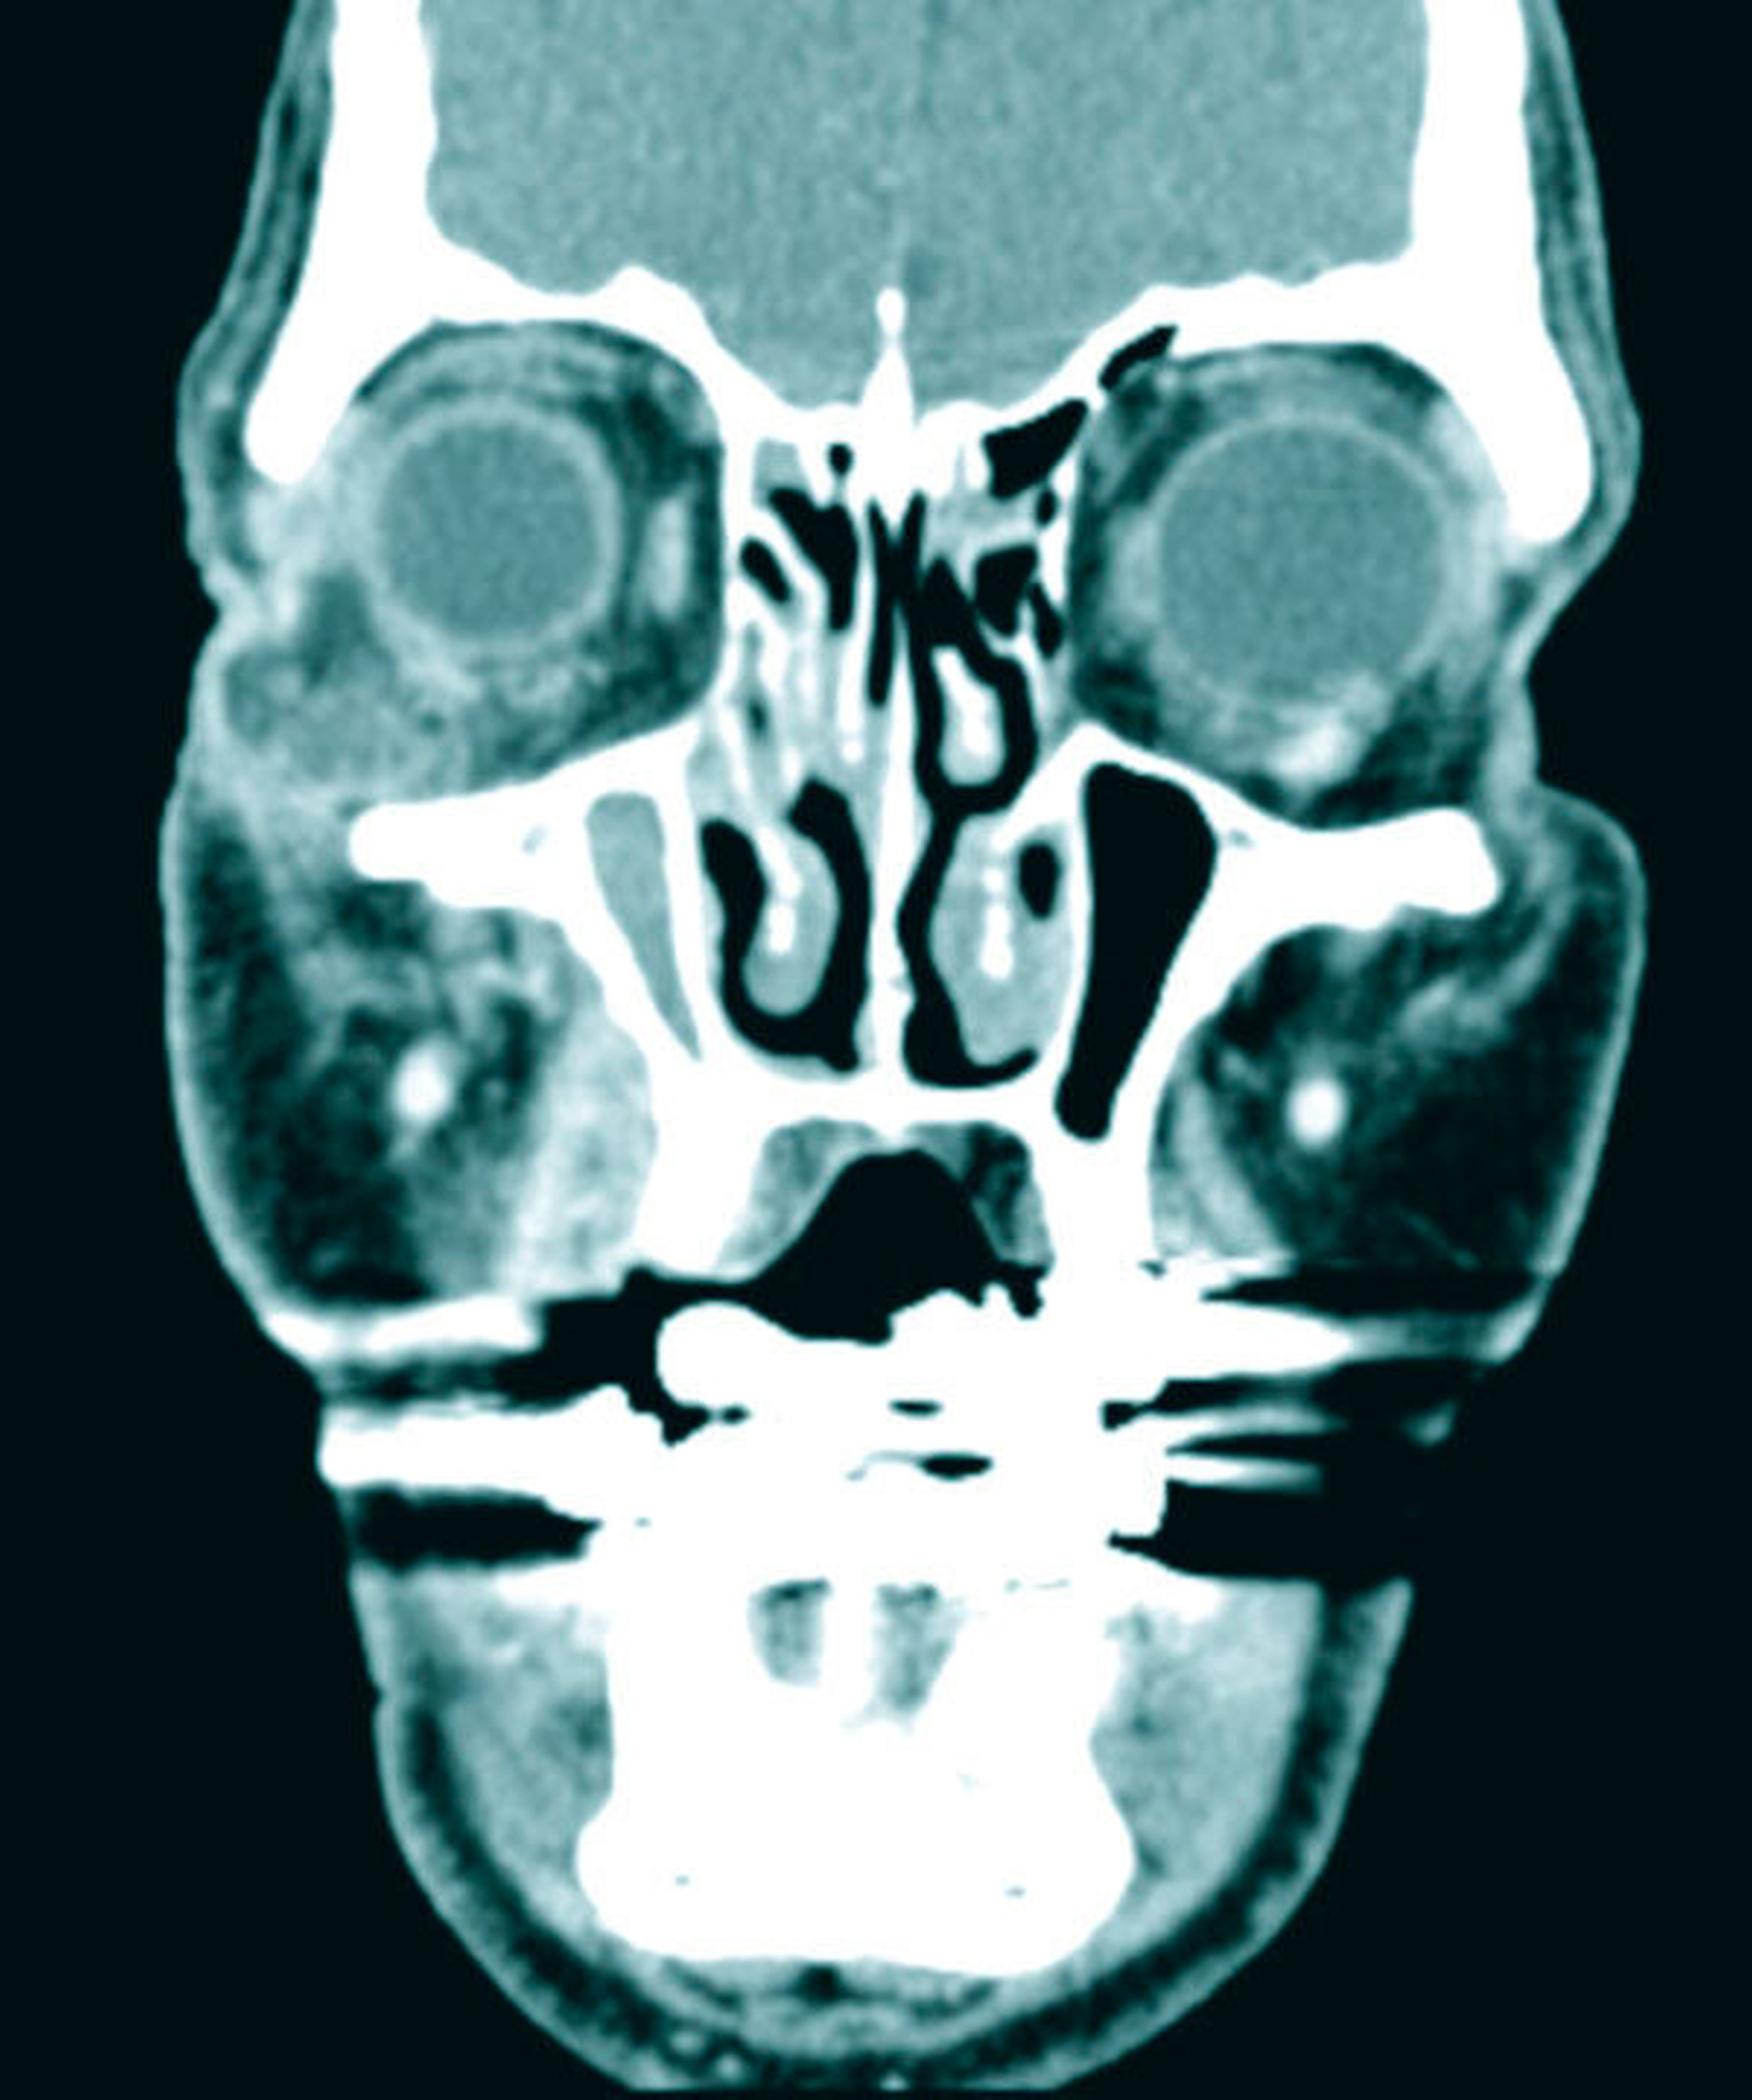

Wegen der unklaren Genese der akuten entzündlichen Veränderungen in der Orbital- und in der Periorbitalregion wurde eine CT- Diagnostik des Schädels mit Kontrastmittelgabe zum Ausschluss einer akuten retrobulbären Raumforderung veranlasst. Hierbei fand sich ein hochgradiger Verdacht auf eine Abszedierung in der rechten Orbita mit dem klinischen Bild von Protrusio bulbi und entzündlicher Mitreaktion der Augenmuskeln M. rectus lateralis und M. rectus inferior. Diese Veränderungen waren auch der Grund für die Weichteilschwellung am Unterlid. Ein intraorbitales Hämatom ließ sich ausschließen.

Zur weiteren Abklärung erfolgte nach zweidimensionaler Beurteilung die dreidimensionale Rekonstruktion der CT-Daten. Hierbei kamen die röntgenopaken Implantate im Kiefer sehr gut zur Darstellung und konnten in Bezug auf deren anatomische Lage beurteilt werden. Im atrophen Ober- und Unterkiefer zeigte sich ein mittelgradiger horizontaler Knochenabbau mit vertikalen Einbrüchen an allen Implantaten. In der rechten Maxilla regio 016 bestand nach Explantation eines rechtsseitigen Zygoma-Implantats ein circa 2 cm großer Defekt, der, aufgrund der verdrängten Weichgewebe und Lufteinschlüsse sicher bis in die mittlere, zentrale Orbita reichte.

Als auffälliger Nebenbefund fand sich auch auf der linken Seite ein 60-mm-Zygoma-Implantat, das 17 mm in die linke Augenhöhle ragte. Neu aufgetretene Veränderungen oder Behinderungen in diesem Bereich waren vom Patienten subjektiv nicht wahrgenommen worden, die Implantation selbst lag bereits zehn Jahre zurück.